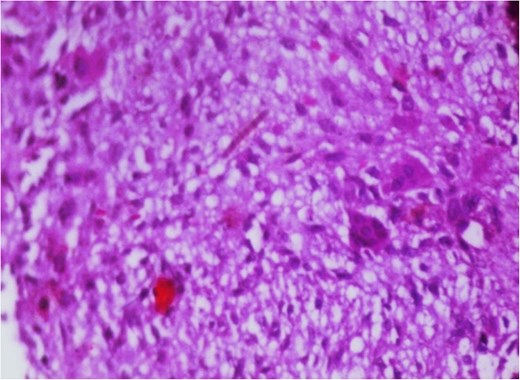

Additionally, magnetic resonance venography (MRV) confirmed a patent superior sagittal sinus with no encroachment of the lesion (Fig. 4). Differential diagnoses included dermoid cyst, eosinophilic granuloma, or benign fibro-osseous lesion. Surgical intervention involved en bloc excision under general anesthesia. A curvilinear incision was made over the mass, followed by subperiosteal dissection, which confirmed the lesion’s confinement to the diploë. Intraoperative frozen section analysis was not performed due to the lesion’s benign radiological features. Histopathological examination confirmed NOF, demonstrating ectodermal inclusion, cellular stroma of spindle-shaped fibroblasts arranged in a prominent storiform pattern, and scattered osteoclast-like giant cells. Notably, no evidence of mitotic figures, nuclear atypia, or necrosis was observed (Figs 5–7). The margins were free of lesional tissue. Postoperatively, the child resumed oral intake within 4 hours and was discharged on postoperative day 2 with analgesics. At the 6-month follow-up, the wound had healed without complications, with no recurrent lesion.

Photomicrograph in a case of NOF showing interlacing bundles of spindle-shaped fibroblasts in a storiform manner, H&E × 100.

Photomicrograph in a case of NOF showing interlacing bundles of spindle-shaped fibroblasts in a storiform manner, H&E × 400.